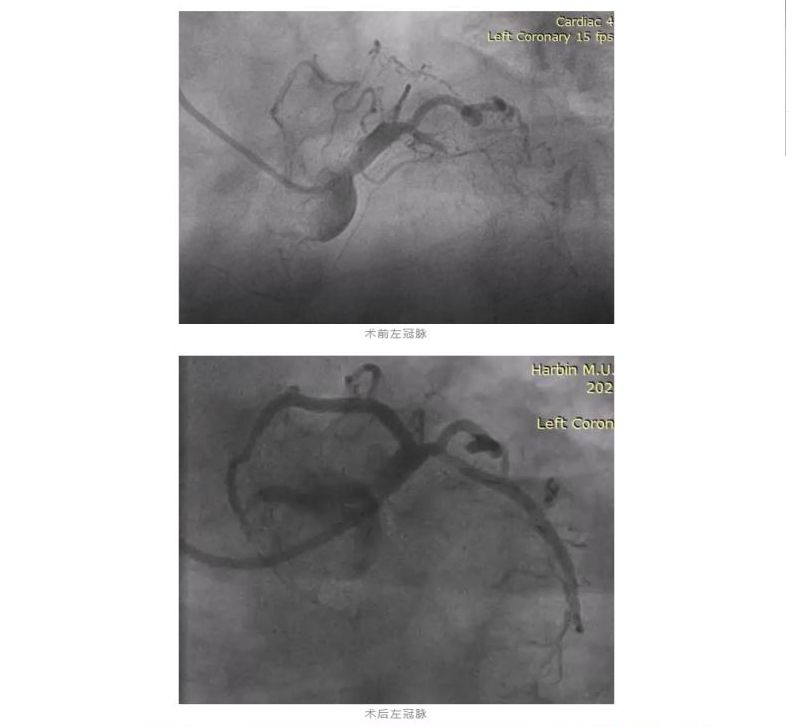

经过评估和准备,医生们先是快速地成功为这位老人开通了一支刚刚闭塞的血管,为患者打开了“生命之门”,使病人的血压能够维持,随后又迅速开通了第二支慢性完全闭塞的病变,心脏得到了血运供应后,老人生命体征逐渐平稳,后续成功开通的第三根慢性闭塞的病变血管,达到了完全的血运重建。